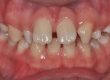

Клинични аспекти при прилагане на апарата Pendulum в смесено съзъбие

В тази статия си поставяме за цел да разискваме от клинична гледна точка позитивите и негативите при ползване на апарата Pendulum в смесено съзъбие. Ще разгледаме становищата за работа с апарата в случаите, когато са включени временните молари като опорна зона. Ще дадем какви са според нас клиничните предпоставки и индикации за използването на Pendulum в смесено съзъбие. Ще разгледаме терапевтичния протокол на няколко клинични случая, решени с прилагането на този апарат. Натрупаният от нас опит показва, че независимо кои зъби са в опорната зона се получава дистализиране на горни молари, но има разлики в не са значителни и не се отразяват негативно на основния ефект от действието на апарата Pendulum. Затова препоръчваме неговото ползване във всяка възраст и дентиция.